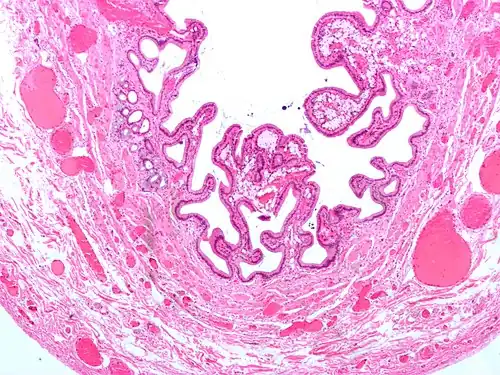

-

Micrograph of cholesterolosis of the gallbladder -